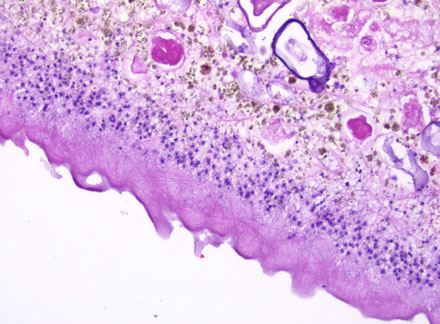

Rathke's Cleft Cyst

Sellar region (pituitary) cyst lined by respiratory-type epithelium

- 2/2 Rathke's pouch not developing properly; may be found in up to 25% of people!

- change in pressure can cause headaches

Tx: drainage and bx